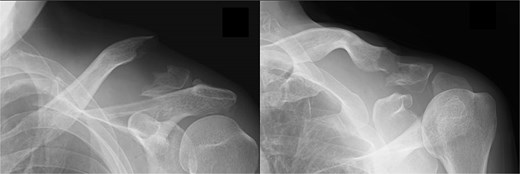

A 66-year-old man presented with left shoulder pain after falling. A Neer Type IIB fracture of the distal clavicle with significant displacement was revealed on radiographs (Fig. 1); however, owing to severe aortic valve stenosis and heart failure, the patient was deemed unfit for surgery. The patient underwent conservative treatment for distal clavicle fracture for 5 months; however, the pain in the left shoulder persisted, and significant skin protrusion caused by a displaced bone fragment was noted. No findings suggestive of neurovascular injury were observed. Radiography and computed tomography (CT) examinations revealed fracture displacement progression (Fig. 2A–C). After undergoing aortic valve replacement 3 months postinjury, the cardiac function of the patient improved and surgery was performed to treat the distal clavicle nonunion.

Radiographs captured immediately after injury show a fracture of the left distal clavicle with displacement.